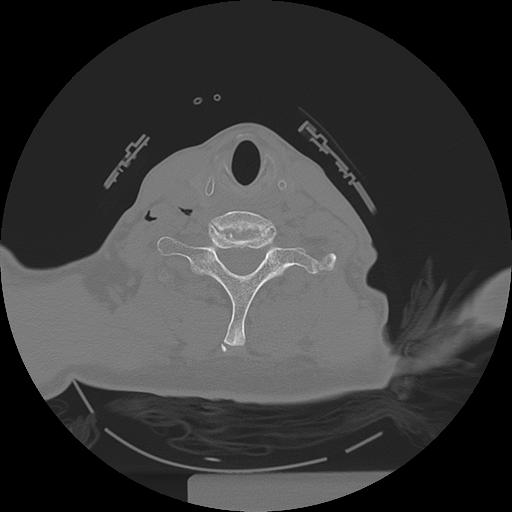

11 HUESO,,Axial,2.0,HUESO,,